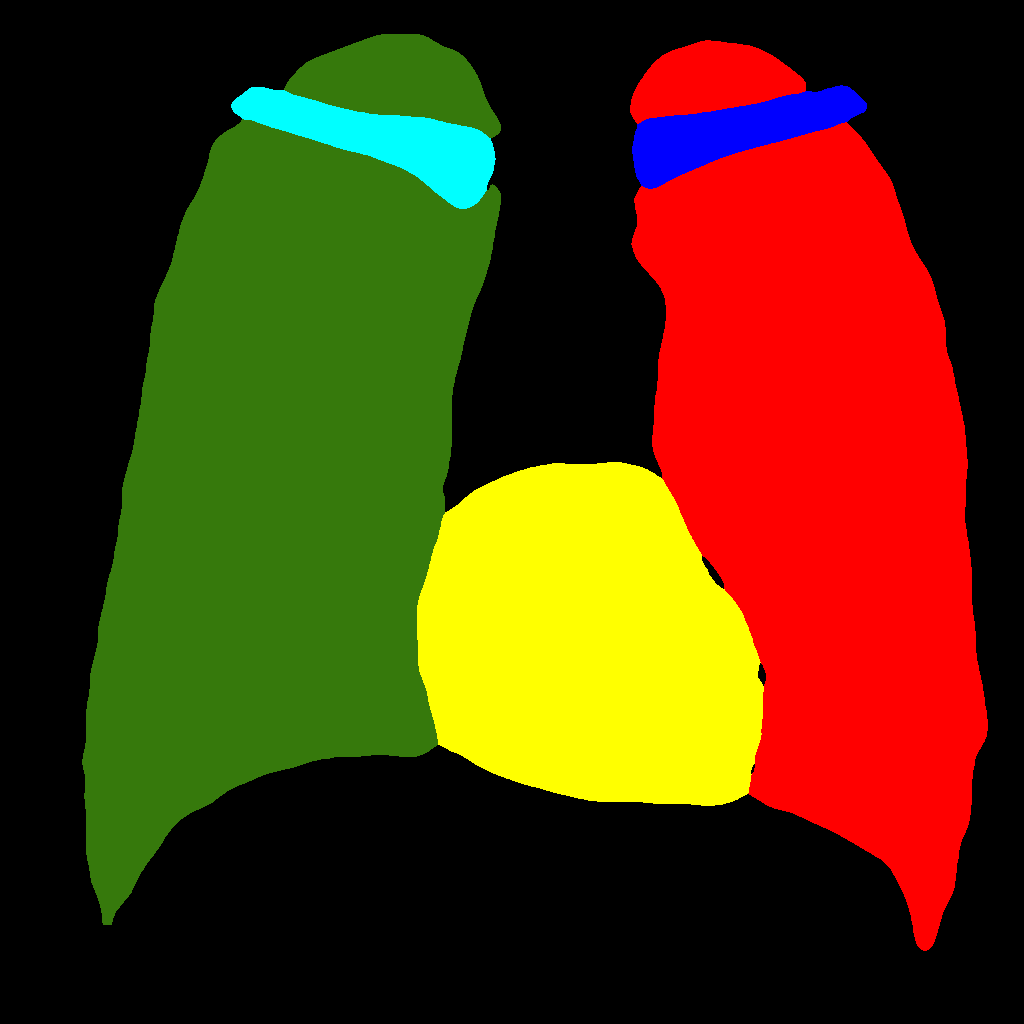

In this section, some examples of images and corresponding segmentations, generated with the approaches described in Section 3, are qualitatively examined. We also report some comments from three physicians on the generated segmentations, to provide a medical assessment of the quality of our method.

Figure 5 and Figure 6 display some examples — randomly chosen from all the generated images — of the label–maps and the corresponding chest X–ray images generated with the three methods described in Section 3, using the FULL_DATASET and the TINY_DATASET, respectively. We can observe that, with the single and two–stage methods, the images tend to be more similar to those belonging to the training set. For example, in most of the generated images there are white rectangles, which resemble those present in the training images, used to cover the names of both the patient and the hospital. Instead, the three–stage method does not produce such artifacts, suggesting that it is less prone to overfitting.

Moreover, in order to clarify the limits of the three–stage method, we assessed the quality of the segmentation results based on three human experts, who were asked to check 20 chest X–ray images, along with the corresponding supervision and the segmentation obtained by the SMANET network. Such images were chosen among those that can be considered difficult, at least based on the high error obtained by the segmentation algorithm. Figure 7 and Figure 8 show different examples of the images evaluated by the experts. The first column represents the chest X–ray image, while the second and the third columns, whose order was randomly exchanged during the presentation to the experts, represent the target segmentation and our prediction, respectively. The three physicians were asked to choose the best segmentation and to comment about their choice. Apart from a general agreement of all the doctors on the good quality of both the target segmentation and the segmentation provided by the three–stage method, surprisingly, they often chose the second one. For the examples in Figure 7, for instance, all the experts share the same opinion, preferring the segmentation obtained by the SMANET over the ground–truth segmentation. To report the results of the qualitative analysis, we numbered the target and predicted segmentation with 1 and 2, respectively, while doctors were assigned unordered pairs to obtain an unbiased result. Then, with respect to Figure 7(a), the comments reported by the experts were: 1) In segmentation 1, a fairly large part of the upper left ventricle is missing; 2) I choose the segmentation number 2 because the heart profile does not protrude to the left of the spine profile; 3) The best is No. 2, the other leaves out a piece of the left free edge of the heart, in the cranial area. Instead, for Figure 7(b), we obtained: 1) The second image is the best for the cardiac profile. For lung profiles, the second image is always better. The only flaw is that it leaks a bit on the right and left costophrenic sinuses. 2) Image 2 is the best, because the lower cardiac margin is lying down and does not protrude from the diaphragmatic dome. Image number 1 has a too flattened profile of the superior cardiac margin. 3) No. 2 for the cardiac profile more faithful to the real contours.

Instead, they reported conflicting opinions or decided not to give a preference with respect to the examples in Figure 8. When they agreed, they generally found different reasons for choosing one segmentation over the other. With respect to Figure 8(a) the comments reported by the experts were: 1) I prefer not to indicate any options because the heart image is completely subverted; 2) Segmentation number 2 is better, even if it is complicated to read because there is a “bottle–shaped” heart. The only thing that can be improved in image 2 is that a small portion of the right side of the heart is lost; 3) No. 1 respects more what could be the real contours of the heart image. Instead, for Figure 8(b) we obtained: 1) I prefer No. 2 because the tip of the heart is well placed on the diaphragm and does not let us see that small wedge–shaped image that incorrectly insinuates itself between heart and diaphragm in image 1 and which has no correspondence in the RX; 2) Both are good segmentations. Both have small problems, for example: in segmentation 1 a small portion of the tip (bottom right of the image) of the heart is missing, in segmentation 2 a part of the outflow cone (the “upper” part of the heart) is missing. It is difficult to choose, probably better No. 1 because of the heart; 3) No. 2 because No. 1 carnally probably exceeds the real dimensions of the cardiac image, including part of the other mediastinal structures.